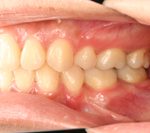

矯正の症例

1) 矯正前の状態

叢生(そうせい…歯がデコボコしたり、重なりあって生えていたりする状態)

開咬(かいこう…奥歯はしっかり噛んでいるが、上下の前歯が噛まずに隙間がある状態)